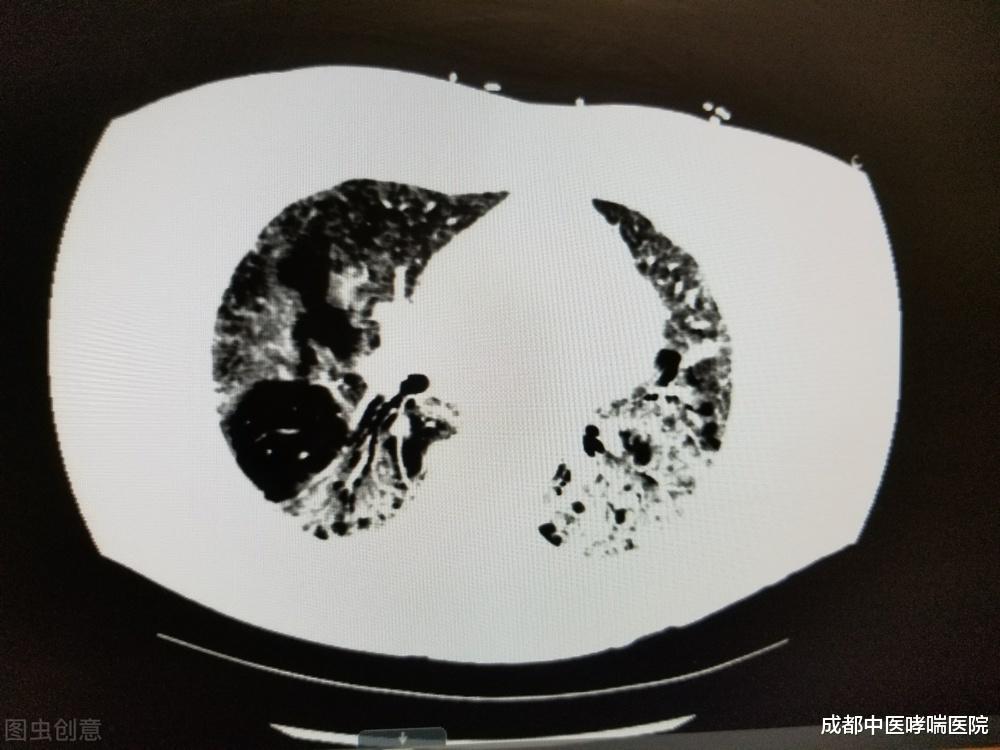

肺气肿重度 , 咳嗽、咳痰、气短症状明显 , 活动耐力明显下降 。

如果肺功能降低到一定程度 , 吃饭、穿衣都困难 。

如果慢性支气管炎进一步发展 , 造成肺泡内压力增高 ,

细支气管和肺泡内压力增高 , 出现肺气肿或者肺大泡 。